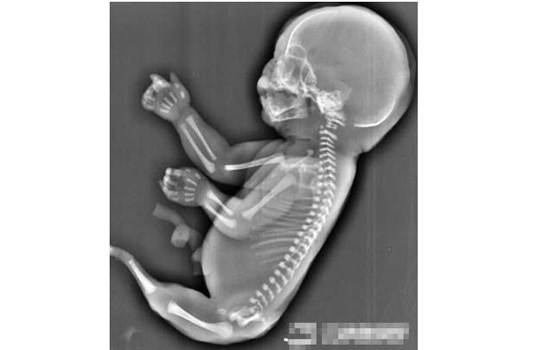

从宜昌市妇幼保健院获悉,吴女士已终止妊娠,当时经超声检查发现孕妇宫腔内未见羊水暗区,借助胎儿骨骼影像顺序连续扫查,发现胎儿头颅、胸腔、双上肢,也可以看到一个跳动的心脏。但下肢只找到一条股骨未见双腿、膀胱,只有一侧发育不良的肾脏。此病全球存活率极低,终止妊娠不失为一个好的方法。

“美人鱼综合征(sirenomelia)”是并腿畸形的俗称,或称人鱼体序列征、尾退化综合征,是一种极为罕见的畸形,男女比例为27∶1。全球6万~10万人中才有1例,患病的新生儿出生后通常只能够存活几个小时。

畸形原因为中后轴中胚层和(或)尾胚层原发缺陷,由于中间尾结构发育不全或有缺陷,造成早期胚下芽融合(腓侧)。此缺陷发生于胚胎原始阶段(妊娠第3周),在尿囊发育之前,故常无尿囊血管。常多种畸形同时存在,或伴发其他畸形,如非瘘的泌尿系统缺陷占19%,生殖系异常占17%,下肢畸形、下脊柱缺陷各占10%。